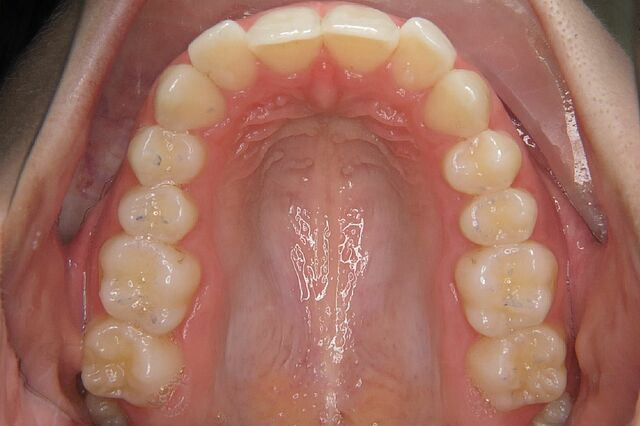

• Engstand

• Tiefbiss

Vorher Nachher Fotos

Tina`s Zahnspange Vorher 0

Tina`s Zahnspange Nacher 0